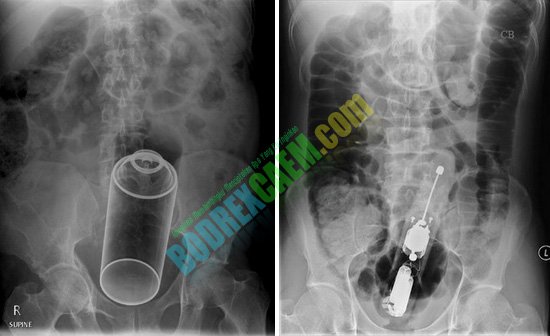

Contoh beberapa foto sinar X di bawah ini, beberap orang mencoba memasukkan benda-benda asing kedalam tubuhnya dan yang terjadi tidak seperti yang dia bayangkan.

Coba perhatikan dengan seksama benda-benda dalam hasil foto sinar x dibawah ini. Dimasukkan ke dalam tubuh lewat mana benda benda tersebut? Saya yakin anda semua akan menemukan jawabannya.